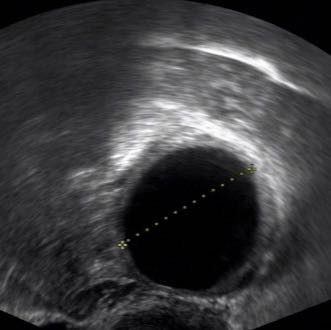

Die Fruchthöhle ist schwarz und deutlich auf dem Ultraschall zu sehen Da durch einen Ultraschall in der 3 Schwangerschaftswoche kein Ergebnis zu sehen ist und die meisten werdenden Mütter noch nichts von einer möglichen Schwangerschaft ahnen, wissen sie es aber ab der 4 SSW, wenn die cm 6'44 cm In der 6. Hier ist der Dottersack nun sehr deutlich zu sehen (man sieht hier auch, wie wichtig die Qualität der Ultraschallgeräts sein kann Der Dottersack wurde hier vermessen und hat einen Durchmesser von 3 Millimetern Der Embryo ist auf diesem Bild noch nicht davon abgrenzbar Ultraschallbild 56 SSW Ein Ultraschallbild vom 6 der 6. Deine vermeidlich 6SSW Ultraschalluntersuchung kann sich also als ein Flopp herausstellen, da man auf dem Ultraschall noch gar nichts sieht Es kann nämlich sein, dass du erst in der 5Schwangerschaftswoche bist, da dein Eisprung erst ein oder zwei e später war oder die Einnistung der befruchteten Eizelle an deiner Gebärmutterwand erst.